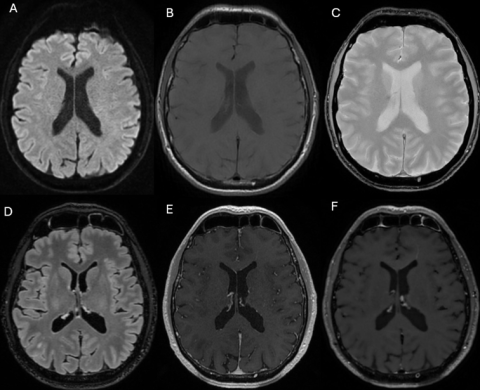

-Protocole court simulé: 3D T2 FLAIR et post-injection 3D T1w-SE

-Protocole long (figure 1): DWI, T2*, 3D T2 FLAIR, T1 natif et après injection 3D T1w-GRE et 3D T1w-SE.

Figure 1.png

Séquences axiales du protocole standard : diffusion pondérée (b = 1000) (A), T1 pondérée sans injection (B), T2* (C), reconstruction axiale 3D-FLAIR avec suppression de la graisse (D), et séquences T1 pondérées après injection 3D en écho de gradient (T1w-GRE) (E) et en écho de spin (T1w-SE) (F).